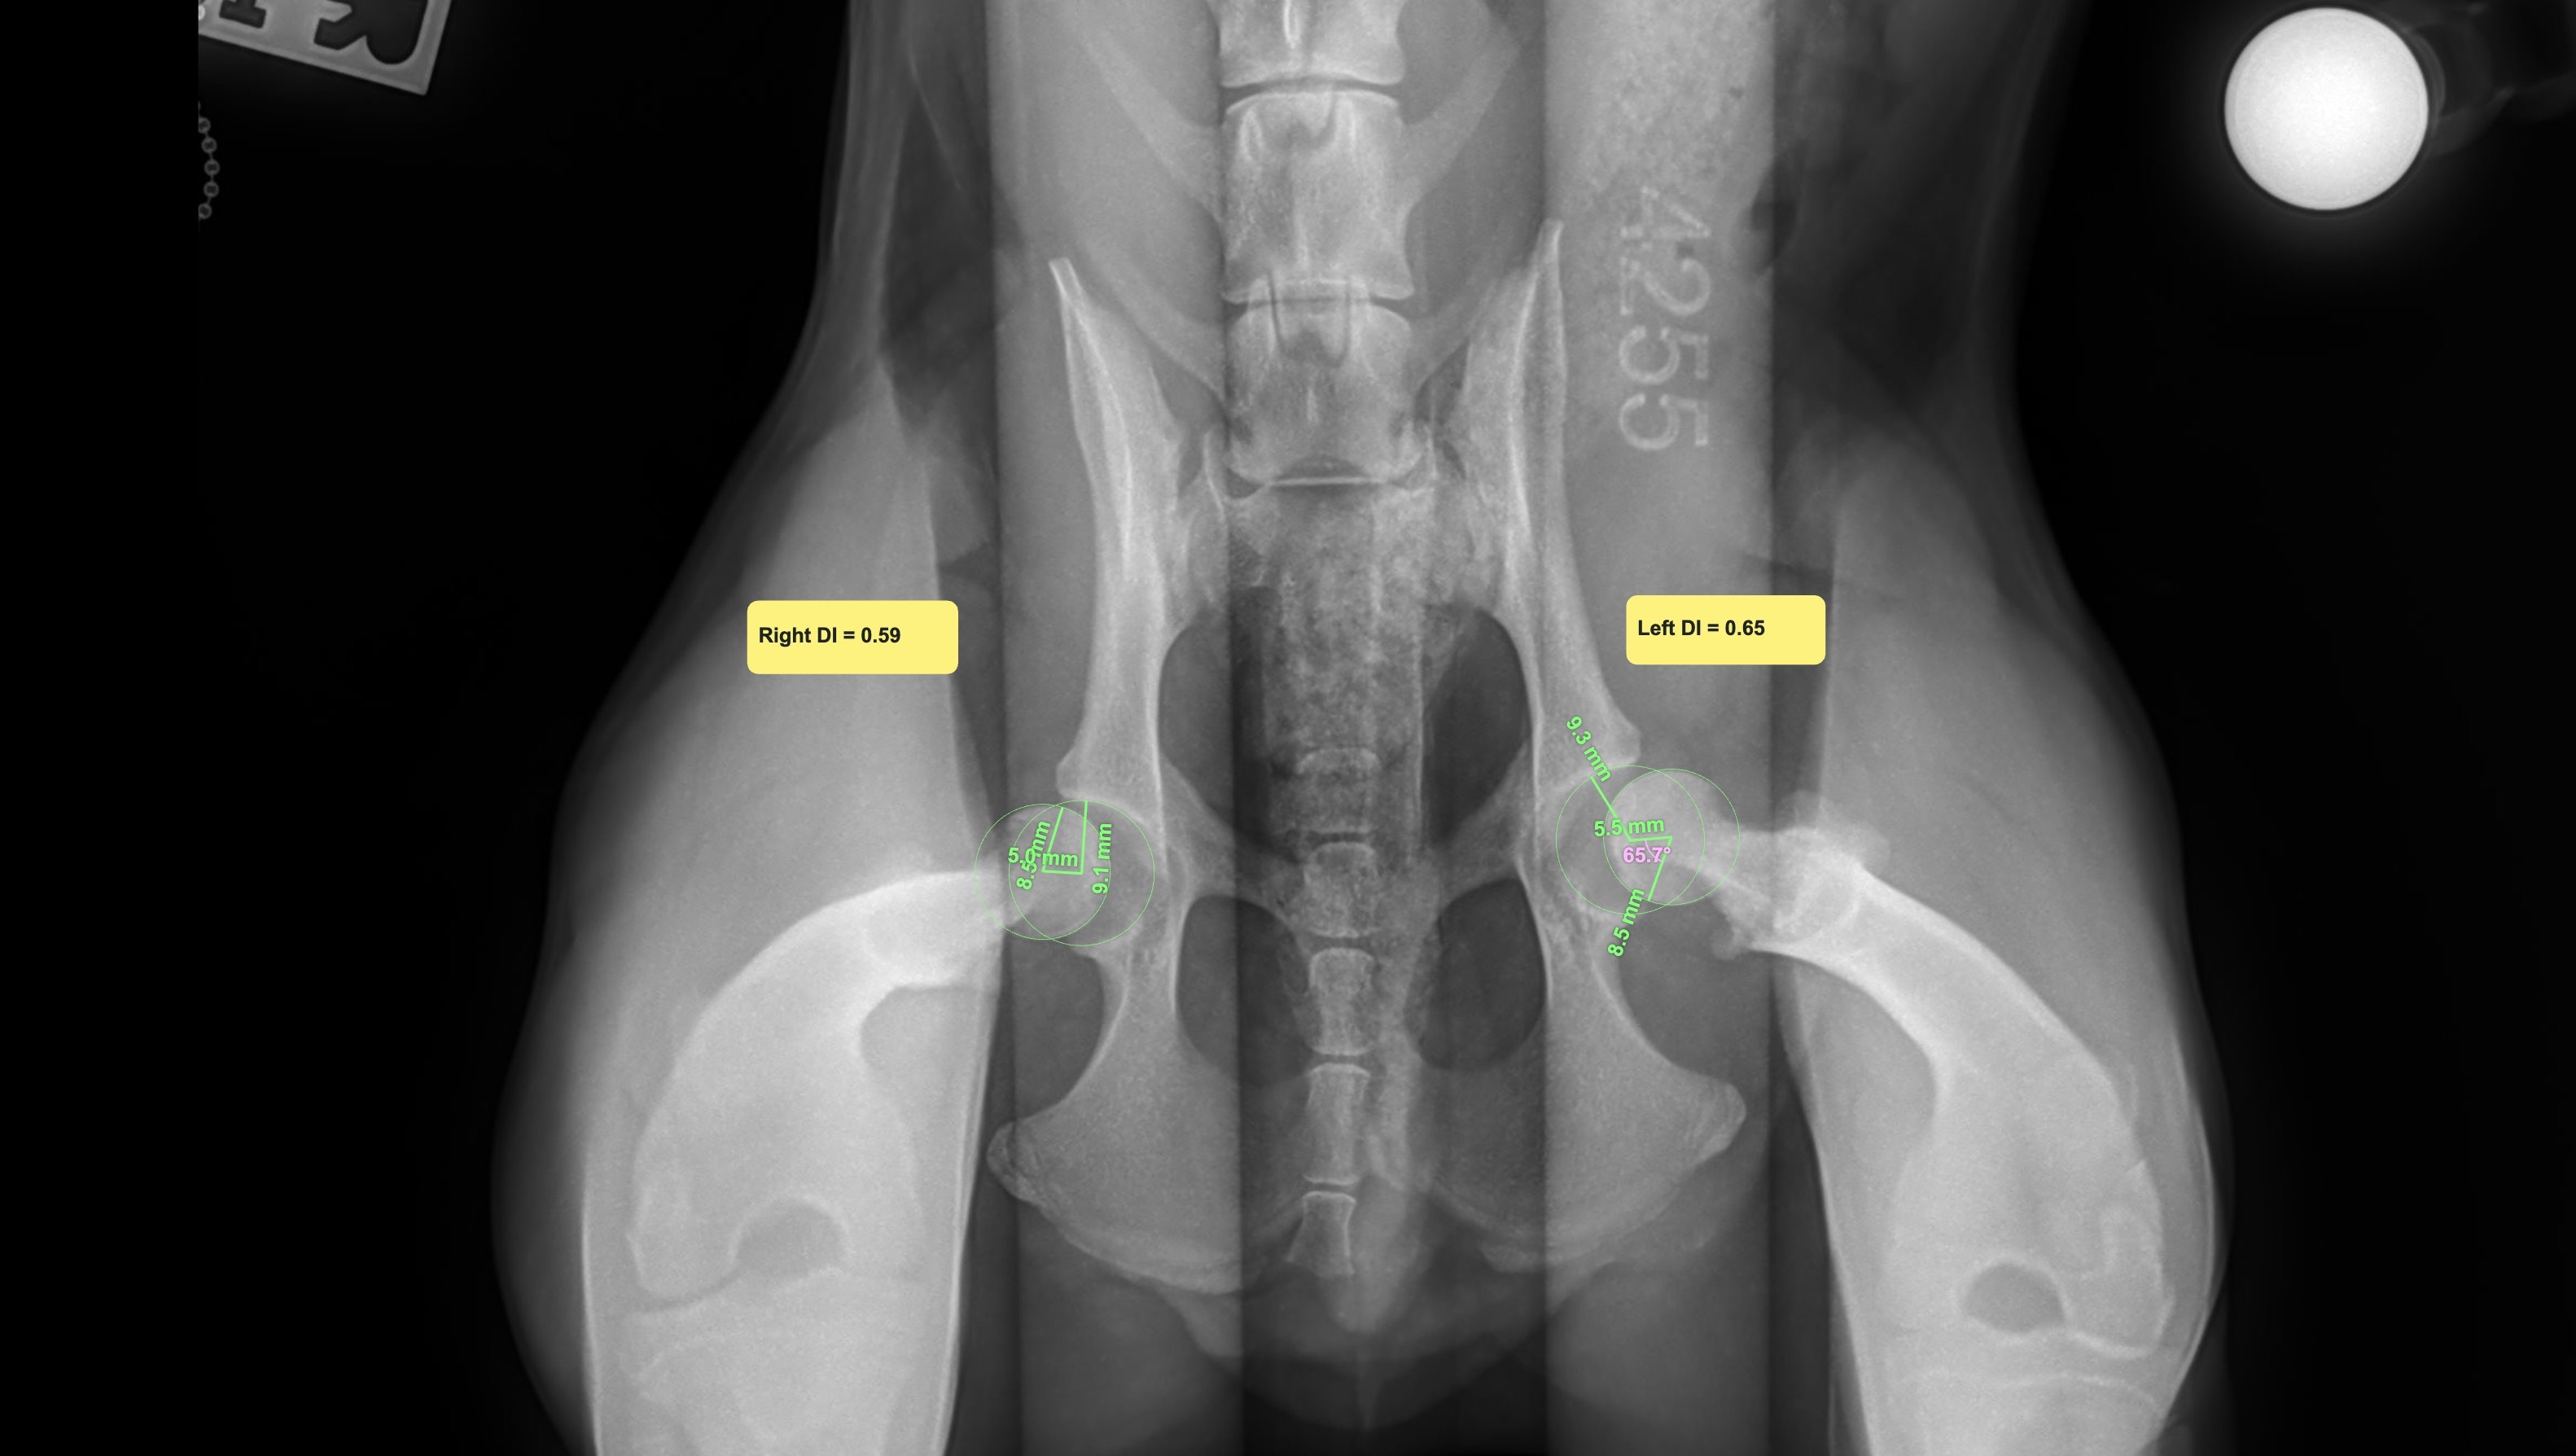

Mylo has since been diagnosed with severe hip dysplasia in both hips and a fracture. He is only 6–8 months old and will need a total hip replacement (THR). The surgery will cost $15,000. Because this all happened so soon after adoption, insurance won’t cover it (most plans have a 30-day waiting period for preexisting conditions).